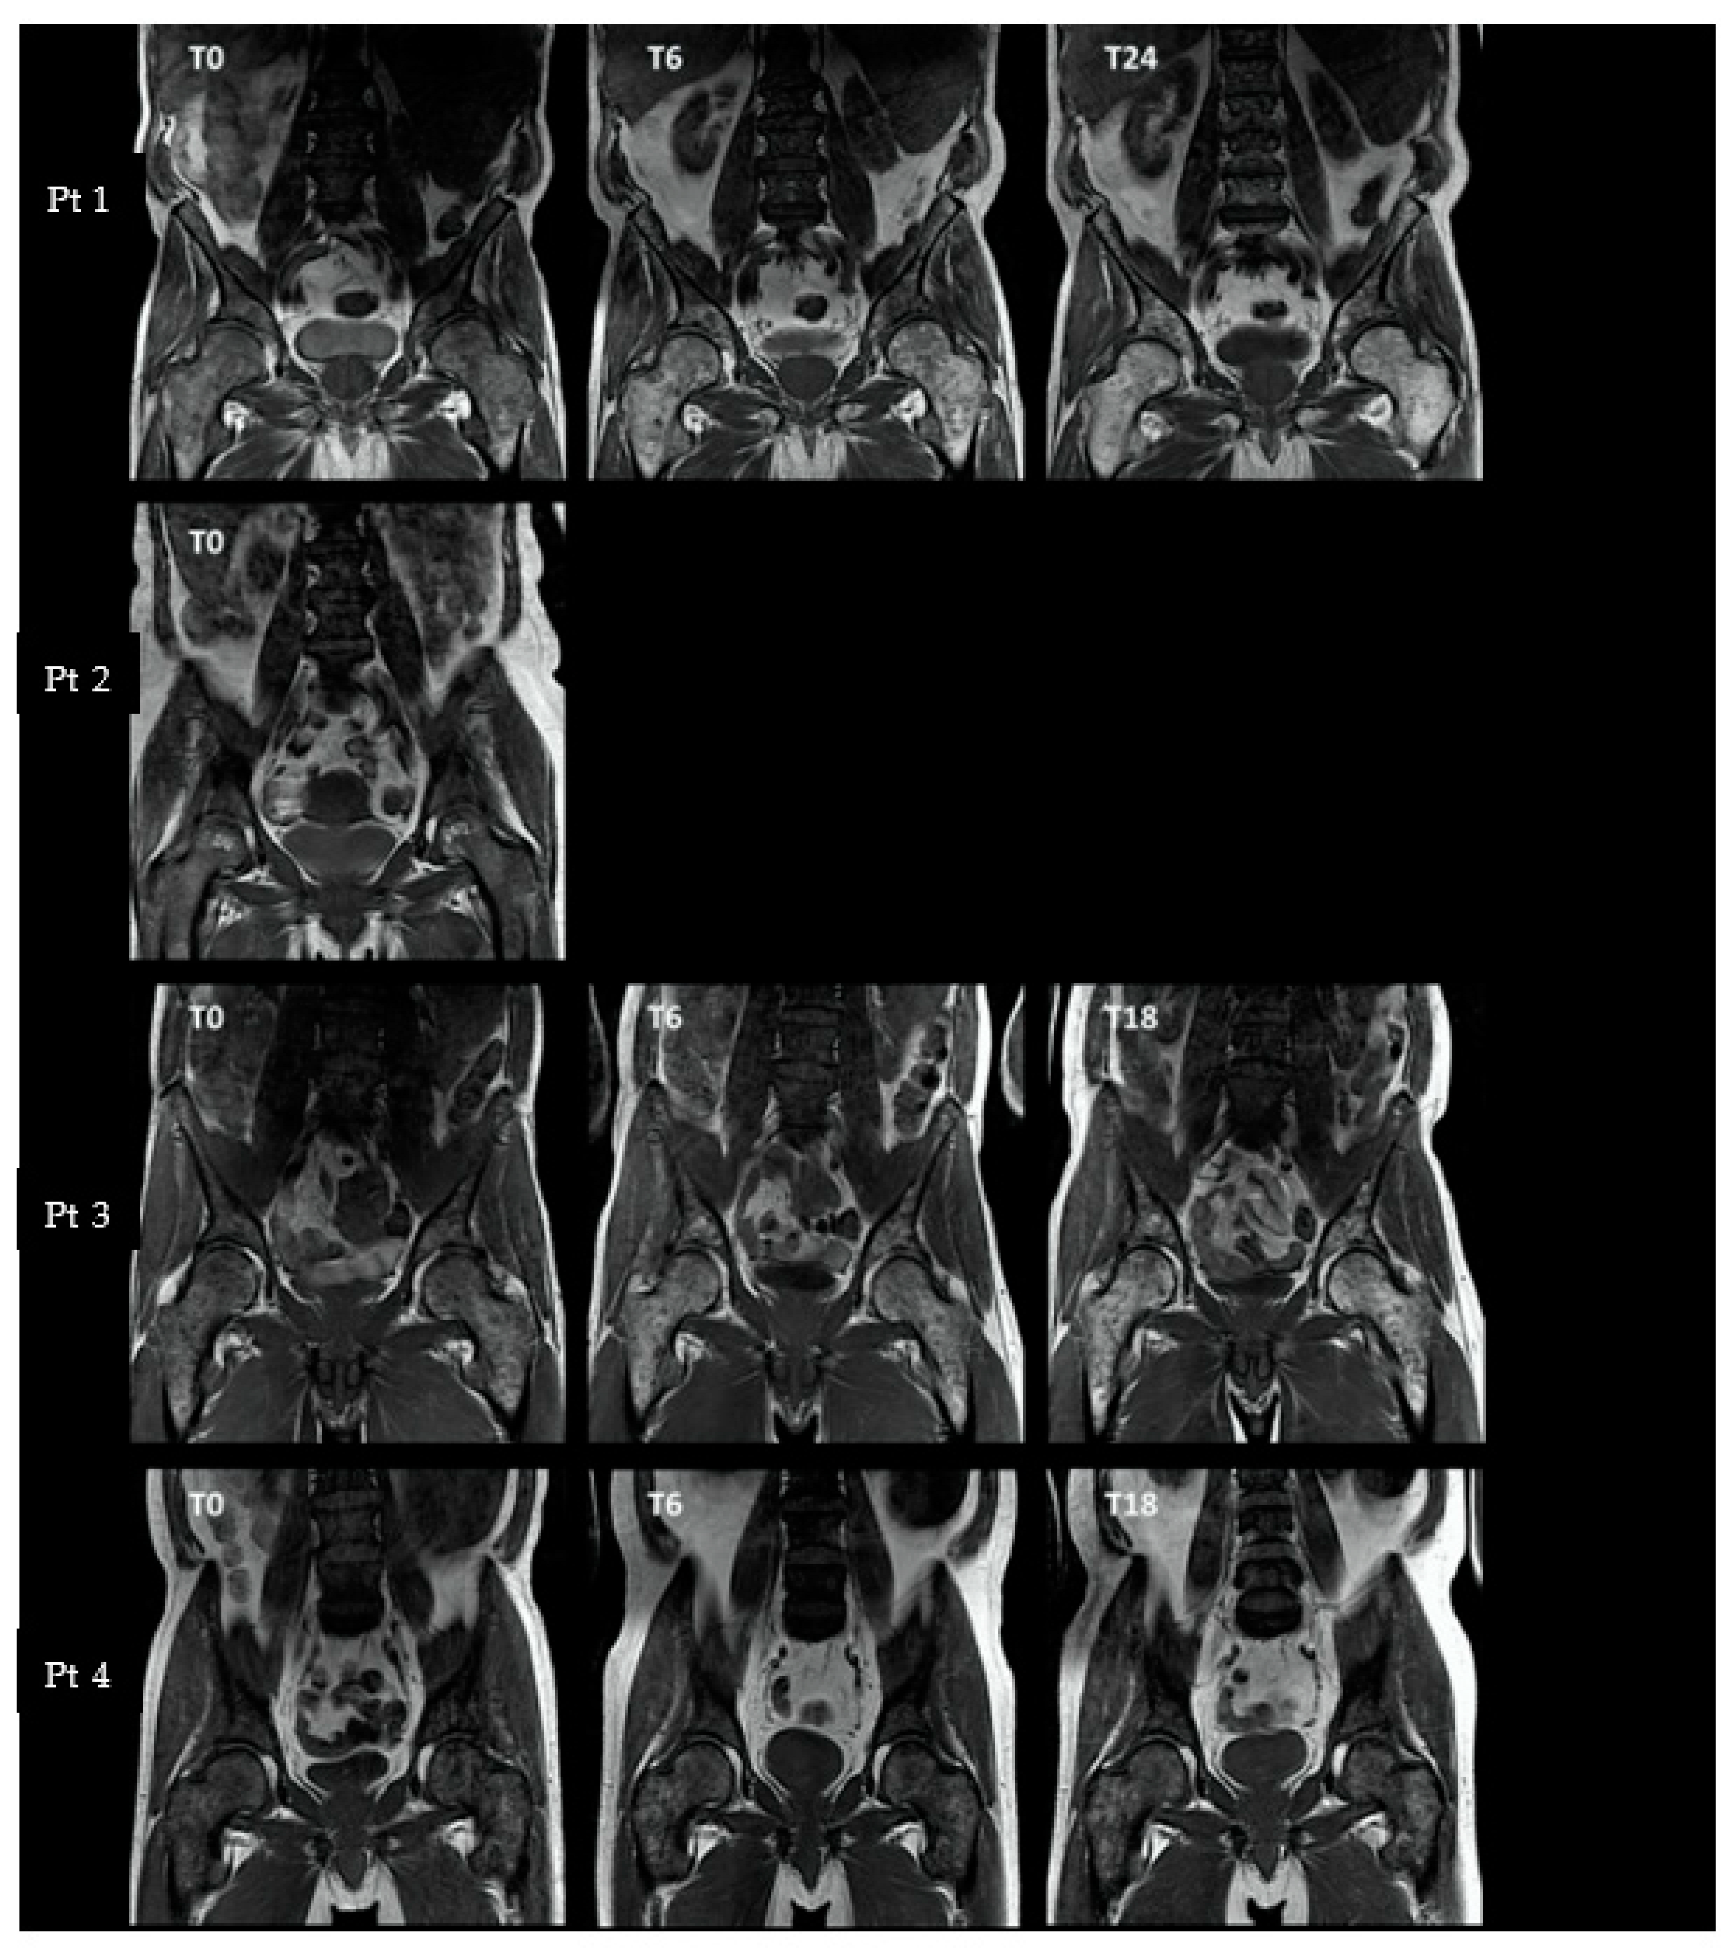

3.3.1. Axial and Proximal Femoral T1-Weighted MRI

| MRI T1 a | Dixon Fat–Water Signal Ratio b | DCE-MRI c (Spine) | 15O-Water PET Flow d (Spine) | 18F-NaF PET SUVintegral e | |||||

|---|---|---|---|---|---|---|---|---|---|

| Pelvis | Spine | Pelvis | Spine | Ve | Ktrans | Pelvis | Spine | ||

| Pt 1 | |||||||||

| T0 | 1-2P | 1P | 0.69 (–) | 0.26 (–) | - | - | 0.33 (–) | 0.08 (–) | 0.08 (–) |

| T6 | 2P | 1P | 1.48 (+114%) | 0.32 (+23%) | +54% | −38% | 0.17 (−48%) | 0.05 (−37%) | 0.08 (=) |

| T24 | 2P | 1-2P | 3.37 (+388%) | 1.32 (+407%) | +90% | −30% | 0.23 (−30%) | 0.05 (−37%) | 0.07 (−12%) |

| Pt 2 | |||||||||

| T0 | 1H | 1H | 0.43 (–) | 0.26 (–) | - | - | 0.40 (–) | 0.12 (–) | 0.11 (–) |

| Pt 3 | |||||||||

| T0 | 1P | 1H | 0.5 (–) | 0.22 (–) | - | - | 0.37 (–) | 0.11 (–) | 0.09 (–) |

| T6 | 2P | 1P | 1.14 (+128%) | 0.28 (+27%) | +11% | +1% | 0.45 (+22%) | 0.12 (+9%) | 0.09 (=) |

| T18 | 2P | 1P | 1.12 (+124%) | 0.16 −27%) | −1% | −13% | 0.54 (+46%) | - | 0.08 (−11%) |

| Pt 4 | |||||||||

| T0 | 1H | 0H | 0.77 (–) | 0.34 (–) | - | - | 0.61 (–) | 0.14 (–) | 0.22 (–) |

| T6 | 1H | 0H | 1.44 (+87%) | 0.76 (+124%) | +33% | +34% | 0.63 (+3%) | 0.17 (+21%) | 0.23 (+5%) |

| T18 | 1H | 0H | 1.34 (+74%) | 0.48 (+41%) | +153% | +185% | 0.66 (+8%) | 0.13 (−7%) | 0.20 (−11%) |